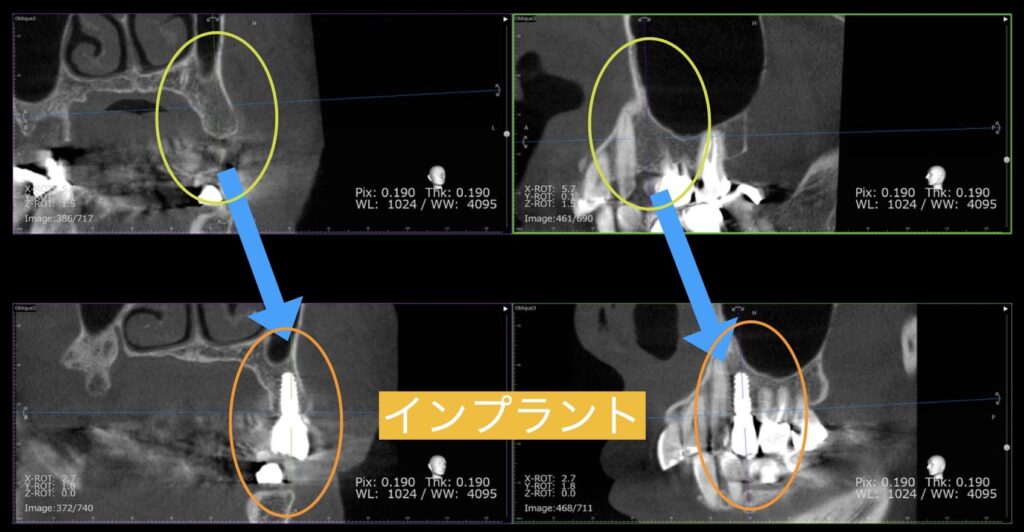

CT画像での確認

サージカルガイドを使用すれば、歯茎を開ける事なく骨の中にインプラントを埋入する事ができます。

歯茎を開けると痛みが大きくなるので、サージカルガイドを使用することは患者様にとって非常に大切なことがわかります。

左上にインプラントを支えるための骨造成をしました。

サイナスリフトといって上顎の空洞に横から骨を挿入しインプラントを植立するための骨を十分に造ります。

合計3本のインプラントを埋入することができました。